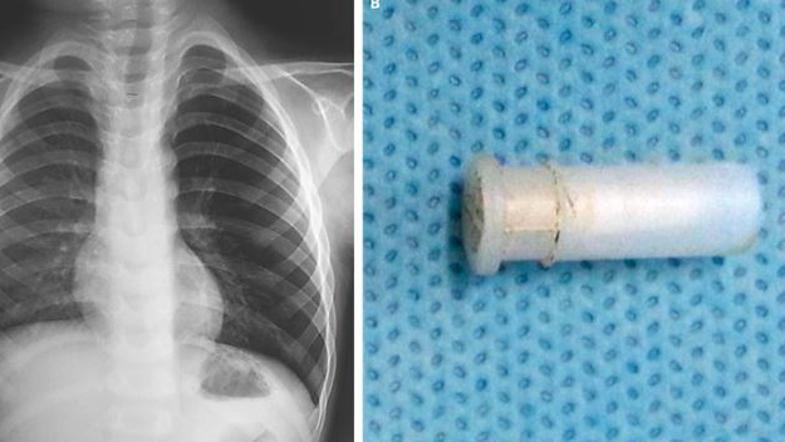

Zaskrbljeni zdravniki so takoj opravili bronhoskopijo in ugotovili, da se v dečkovih pljučih nahaja igrača - piščalka. "Tuja telesa v dihalnih poteh so pogost pojav, živžgajoči kašelj ob tem pa je izjemno redek,"  je za Live Science dejal Dr. Pirabu Sakthivela z Indijskega inštituta za medicinske vede.

Igračo, ki jo je štiriletnik pogoltnil dva dni prej, so mu odstranili in fant je danes zdrav.